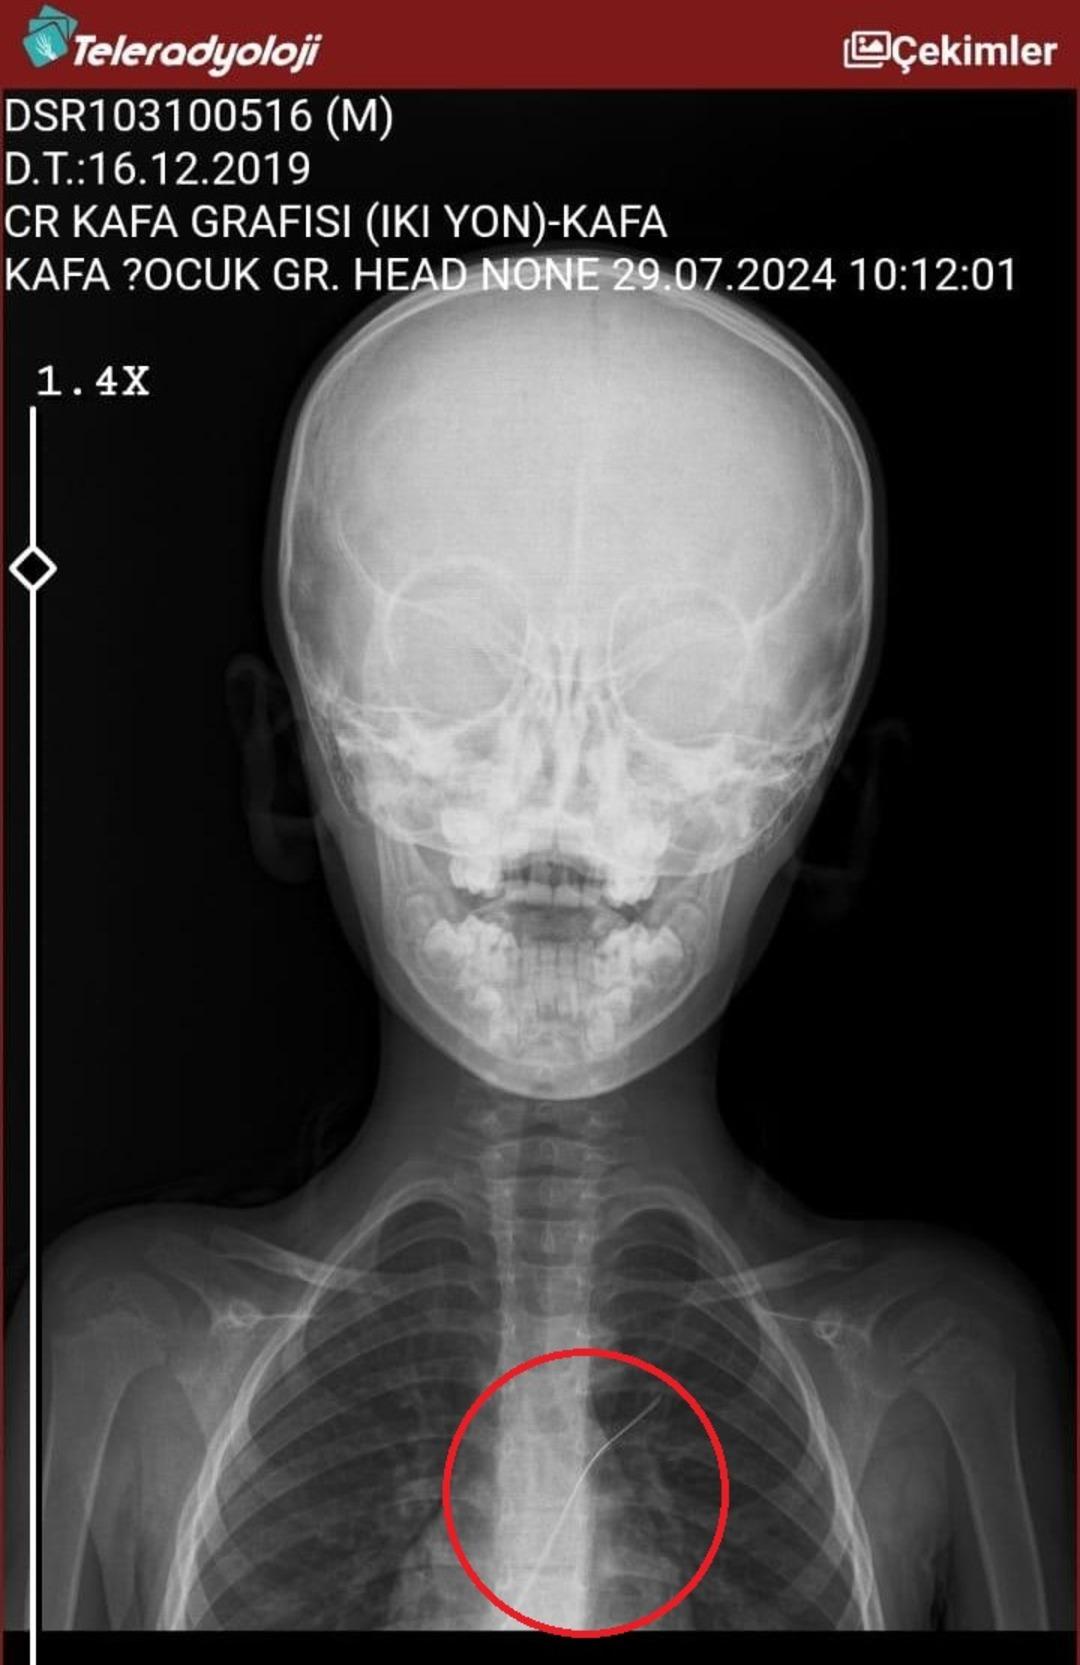

Seamore (37) ve Şaç'ta yaşayan Mehmet Ötün (40), Mayıs ayında bir parça salatalık yuttuktan sonra öksürük ve kusma şikayetleri gözlendiğinde Sernak Eyalet Hastanesine getirildi. Burada, ARAM gövdesinde yarıçap X ve manyetik rezonans görüntüleme unutuldu. Diyarbakir Gazi Yeşargil'in eğitim ve araştırma hastanesi jinekolojiye ve ARAM'lar için ek binaya yönlendirildi, 18 santimetrede 5.5 saatlik riskli cerrahi kaldırıldı. Postoperatif araştırmalarda, kateter kalp kapakına ve karaciğere zarar vermeye kararlıydı.

Aile avukatı Ahmet Yalçın, ikisinin de hastaneden şikayet ettiğini ve bir dava açtığını açıkladı ve şunları söyledi: “Müvekkilim Eylül 2022'de Stevens -Johnson'un kariyeri nedeniyle Eylül 2022'de Dicole'deki üniversite hastanesinde tedavi edildi. Kateter ona saldırıya uğradı.